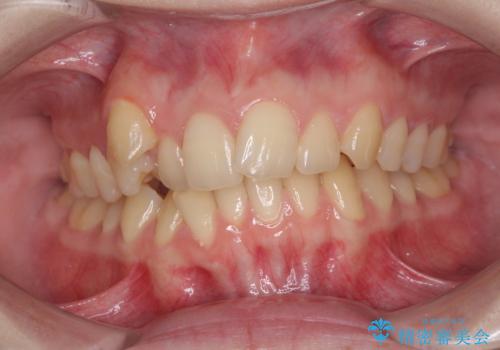

- 著しい八重歯を気にして来院された患者様です。

片側の八重歯であり上顎の正中がずれていたため、上顎左右第一小臼歯2本を抜歯して排列することとしました。